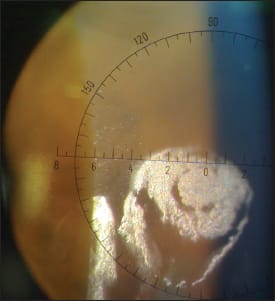

I looked at her lenses with the slit lamp and saw the deposit shown in Figure 1. It had a glistening appearance and didn't look like a jelly bump or other typical deposit. She removed the lens, and I tried to clean it with an extra-strength cleaner. Some of the deposit came off but not all of it.

Figure 1: Contact lens deposit, presumably from makeup.